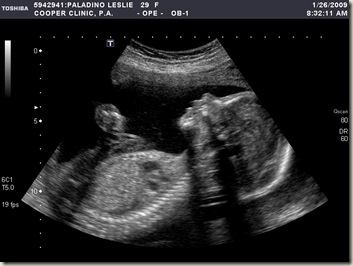

We had our first official ultrasound today and found out that we're having a boy.  I had a very quick surprise ultrasound last week at the dr's office and thought that it was a boy but it was definitely confirmed today.  He's about 1 lb and they have him due about the same time as our original due date so we'll just say June 1st still.  He was very active and healthy.  We've included a video and pictures.  As you can see his little legs are up by his head so he's quite flexible.  Just in case you can't tell what's what in the video his head is on the right and his heart is in the middle of the screen.  His legs are on the left and they extend up to his head.  Sometimes the screen will switch to a foot or hand shot and when they show his profile you can see his tongue moving and his little mouth opening and closing (I think he's saying Mama).

You can see his little foot up on his head.

His arm is extending out and he's pointing to the right here with his little finger.